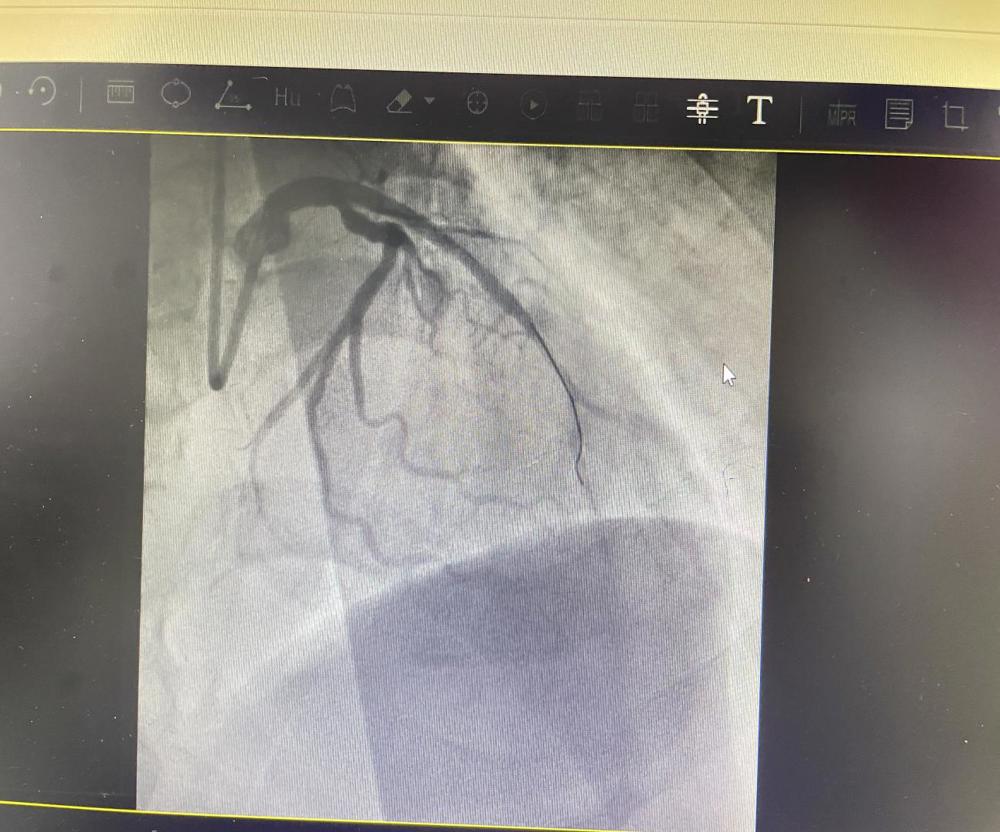

术前准备时,范叔突发室速、室颤、呼吸停止,急诊科团队临危不乱,对其给予电复律、电除颤、心肺复苏等进行抢救。范叔恢复心率后,心内科介入团队立即经右桡动脉行冠脉造影结果示:前降支近段急性闭塞,予行前降支PTCA+血栓抽吸+支架置入术。术后患者恢复自主意识,胸痛症状缓解,但是生命体征不稳定,转入ICU 进一步治疗。

开通血管后